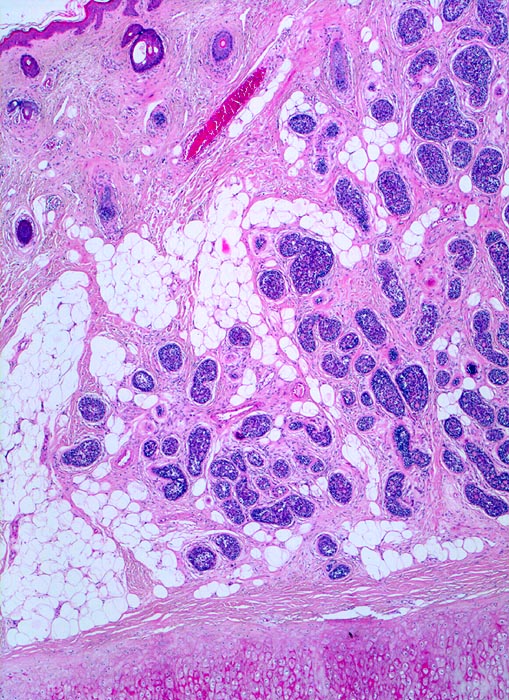

PathoPic ID 3962 - adenoidzystisches Karzinom der Haut

adenoidzystisches Karzinom der Haut

maligner Tumor

Haut, Kopf

Haut

Solide scharf begrenzte unregelmässig in der Dermis und im subkutanen Fettgewebe verteilte Tumorzellnester. Unten im Bild Anschnitt des Ohrknorpels.

Tumor an der Ohrmuschel

Histologie

25

55